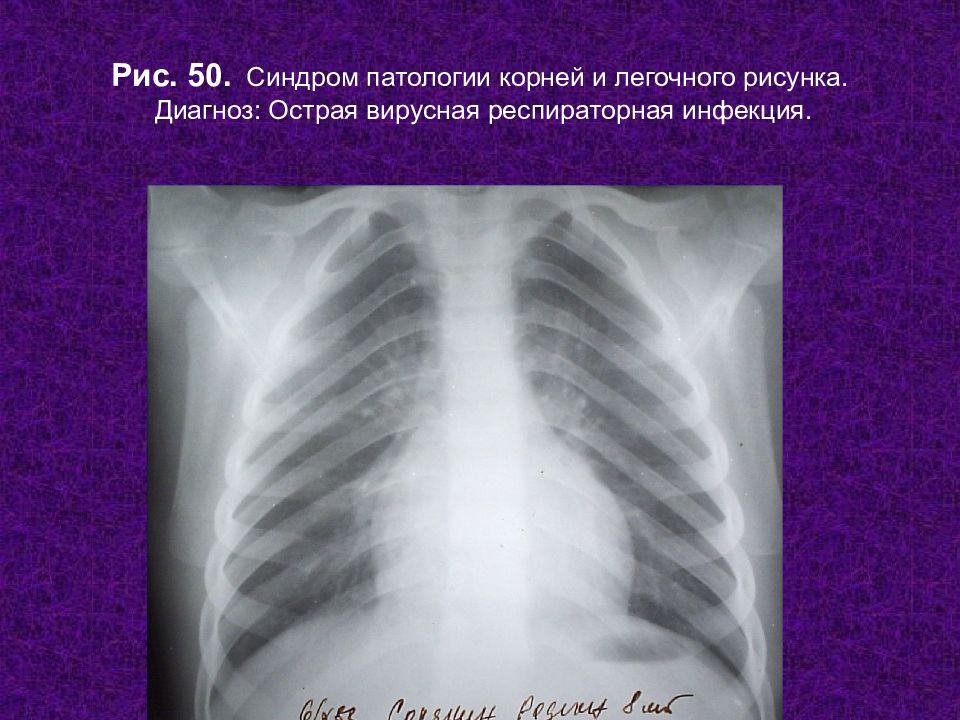

Рентгенологические изображения и синдромы патологии легких

Раздел: Кадры-подсказки